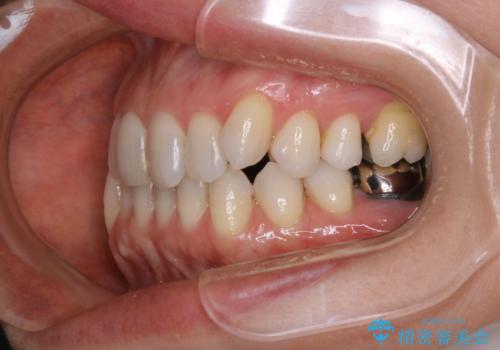

- 右上の小臼歯が二本とも90度捻じれてしまっており、奥歯の噛み合わせに問題が生じていました。

歯を抜いてワイヤー治療を行うという選択肢もありましたが、

奥歯の被せ物の形を適切にすることで非抜歯でも治療が可能であると判断し、

非抜歯、インビザラインでによるマウスピース矯正治療を行うことにいたしました。

今回は右上の奥歯に入っていた銀歯の形が悪く、そのせいで歯を並べるスペースが足りない状態でした。

右上の歯の被せ物を作りなおし、適切な歯の大きさに代えてあげることによってスペースを作りました。

また、それだけではスペースが足りない為右上の奥歯は遠心移動を行っています。